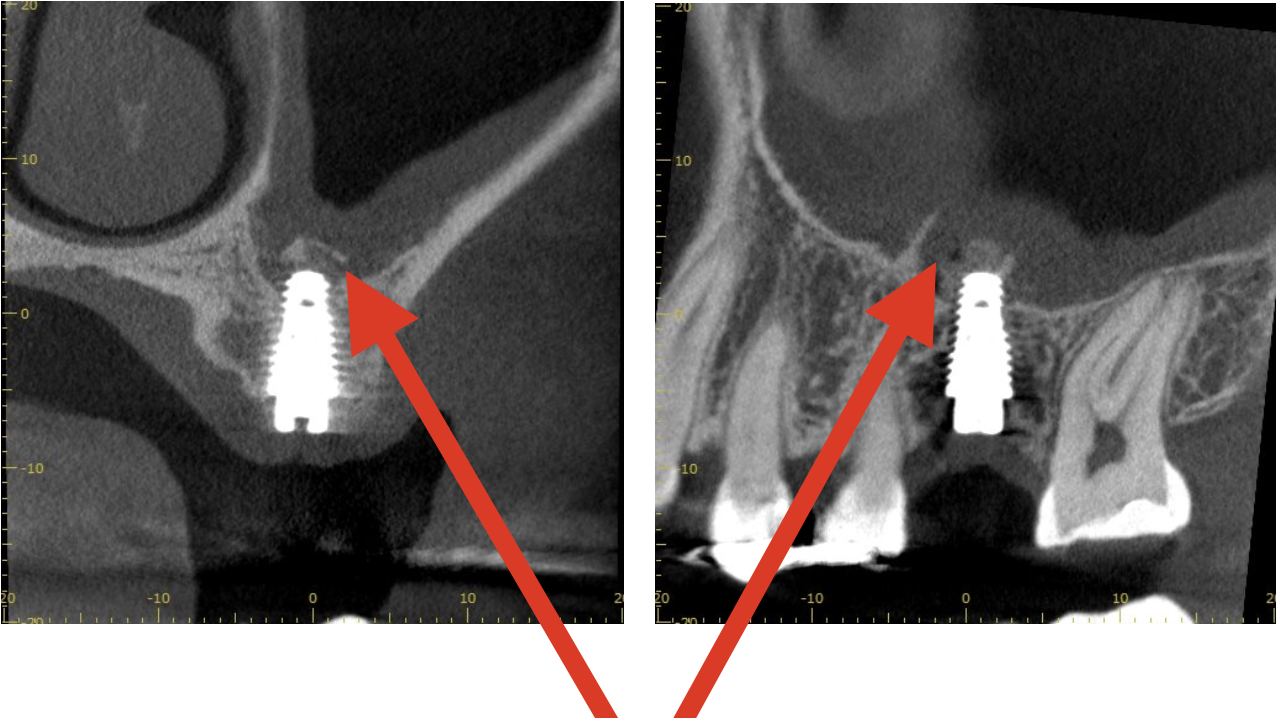

左上を抜歯後インプラント希望のため、CT撮影

骨の高さが少し足りないためクレスタルアプローチを実施しました。

クレスタルアプローチによって骨を3㎜挙上